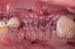

When performing extensive GBR, we want to insure the primary closure of the flap margins over the graft and membrane. In this example, following the placement of the DALI Bone graft and OsseoSeal membrane, the buccal flap was released from the periosteum for passive mobilization (Pictures 1,2,3,4). Prior to suturing the flap margins together at the crest, a periosteal-relief suture is placed in order to prevent any tension from pulling back the flaps (Picture 5). This allows the flaps to stay relaxed without needing to be pulled together. Afterwards, sutures are used to approximate the buccal and palatal flap margins to achieve primary closure that will endure throughout the initial healing period (Picture 6). We see that following 2 weeks of healing, proper primary closure allowed the grafted site to remain covered (Picture 7).